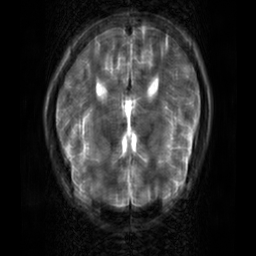

Reconstructing magnetic resonance (MR) images from undersampled data is a challenging problem due to various artifacts introduced by the under-sampling operation. Recent deep learning-based methods for MR image reconstruction usually leverage a generic auto-encoder architecture which captures low-level features at the initial layers and high?level features at the deeper layers. Such networks focus much on global features which may not be optimal to reconstruct the fully-sampled image. In this paper, we propose an Over-and-Under Complete Convolu?tional Recurrent Neural Network (OUCR), which consists of an overcomplete and an undercomplete Convolutional Recurrent Neural Network(CRNN). The overcomplete branch gives special attention in learning local structures by restraining the receptive field of the network. Combining it with the undercomplete branch leads to a network which focuses more on low-level features without losing out on the global structures. Extensive experiments on two datasets demonstrate that the proposed method achieves significant improvements over the compressed sensing and popular deep learning-based methods with less number of trainable parameters. Our code is available at https://github.com/guopengf/OUCR.